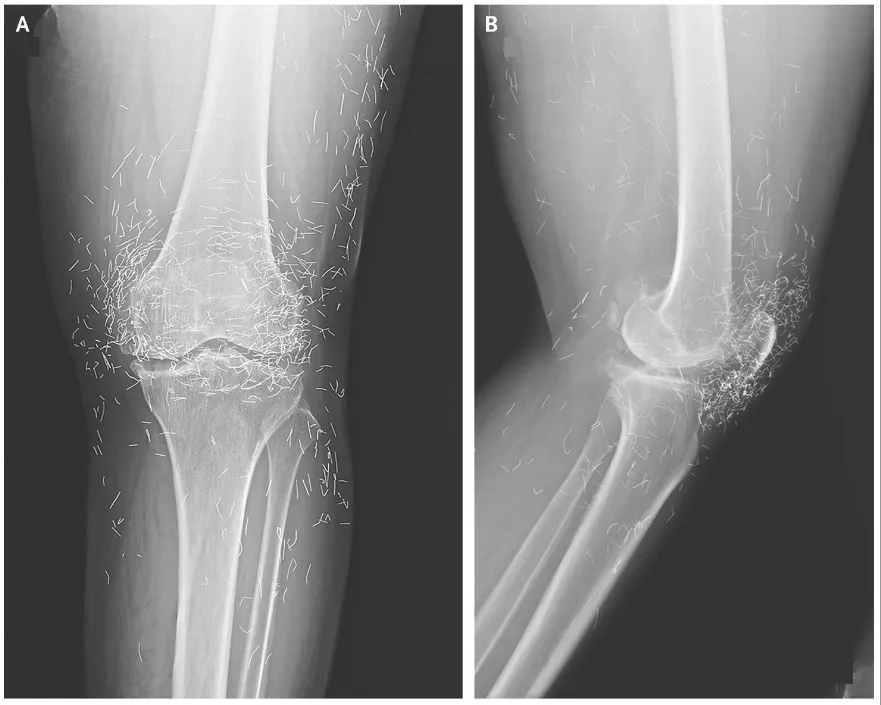

Al acudir nuevamente al hospital por dolor intenso en la rodilla, los médicos realizaron radiografías que mostraron engrosamiento y endurecimiento de la tibia, además de espolones óseos. Lo más sorprendente fueron cientos de diminutos hilos dorados incrustados alrededor de la articulación, insertados durante la acupuntura para estimular el tejido de forma continua. Aunque estos hilos son visibles en radiografías, su presencia no está exenta de riesgos: pueden migrar, dañar tejidos cercanos o formar quistes. Su hallazgo subraya la importancia de conocer los antecedentes de tratamientos alternativos antes de realizar estudios de imagen.

La acupuntura con hilos de oro se utiliza en Asia para tratar artrosis y artritis reumatoide, pero carece de evidencia científica sólida. Además de los riesgos físicos, como migración de hilos y daño a tejidos, puede retrasar el inicio de tratamientos médicos adecuados, empeorando la enfermedad. También puede complicar procedimientos de diagnóstico, como resonancias magnéticas, debido a la presencia del metal. Los profesionales de la salud recomiendan que los pacientes conozcan estos riesgos y que los hilos sean monitoreados si se dejan en el cuerpo, aprovechando su visibilidad en radiografías.